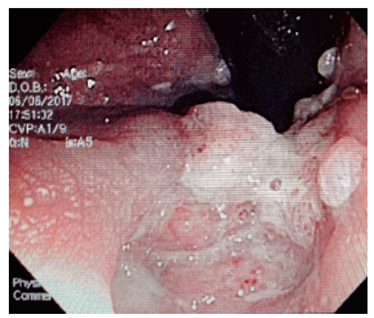

En pacientes con VIH, el citomegalovirus (CMV) genera altas tasas de morbimortalidad y puede afectar cualquier porción del tracto gastrointestinal. Se manifiesta con fiebre, pérdida de peso, anorexia, dolor abdominal y diarrea sanguinolenta. La colonoscopia es el método diagnóstico de elección que evidencia en la mucosa eritema en parches, erosiones y úlceras 20,21.

Varios estudios han demostrado la utilidad de los procedimientos endoscópicos en este contexto. Se debe aclarar que no hay un patrón endoscópico típico de infección por oportunistas, por tanto, siempre se deben tomar biopsias. Se sugiere que la infección por Salmonella predomina en el colon derecho y va desde un eritema hasta ulceraciones. La infección por amebas suele afectar el ciego y rectosigmoide, con ulceraciones y zonas de necrosis (Figura 4 ). El CMV puede generar ulceraciones que predominan en el colon izquierdo (Figura 5 ). El rendimiento de la colonoscopia va desde el 27% al 39%, y el CMV es el germen más común 38.